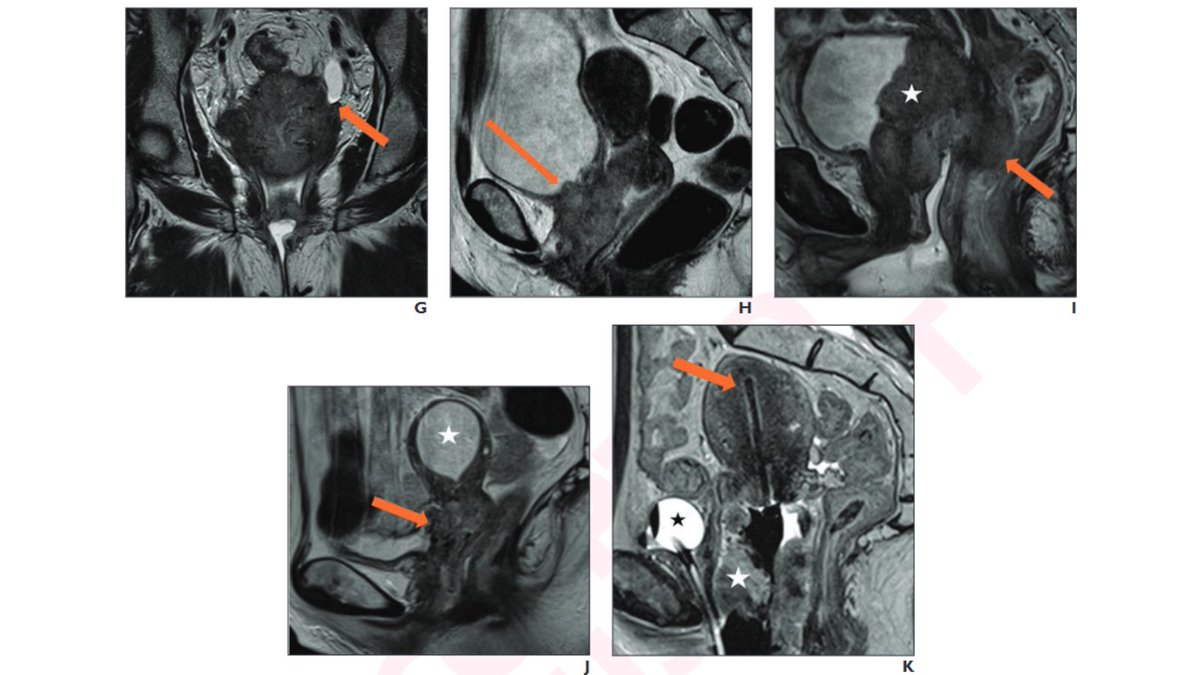

Fantastic workshop by @RadITrainEditor and Shaun Wahab on #ovarian_cancer staging #SAR2022 Pelvic Imaging DFPs of SAR

Shaun Wahab delivers an excellent keynote talk on O-RADS #ARRS23 Use the O-RADS app and online MRI calculator (oradsmricalc.com) for getting familiar with the system American College of Radiology

Congrats to Melissa McGettigan & co-authors Shaun Wahab, Krupa Patel-Lippmann, EricaSteinMD (she/her/hers) & Michael Montejo on our #RSNA23 exhibit (OBEE-9): ‘Cervical Cancer: Beyond Diagnosis’ - a comprehensive, contemporary review of imaging-based management. #PayingitForward #GoTeam #EndCancer

Congrats to my Pelvic Imaging DFPs of SAR colleague Shaun Wahab for moderating & presenting GYN Onc cases during the GU Advanced Cases Audience-Based Participation Session (T7-CGU03). #WomensHealth #EndCancer #RadiologyExcellence #RadiologyEducation #MedEd #RSNA